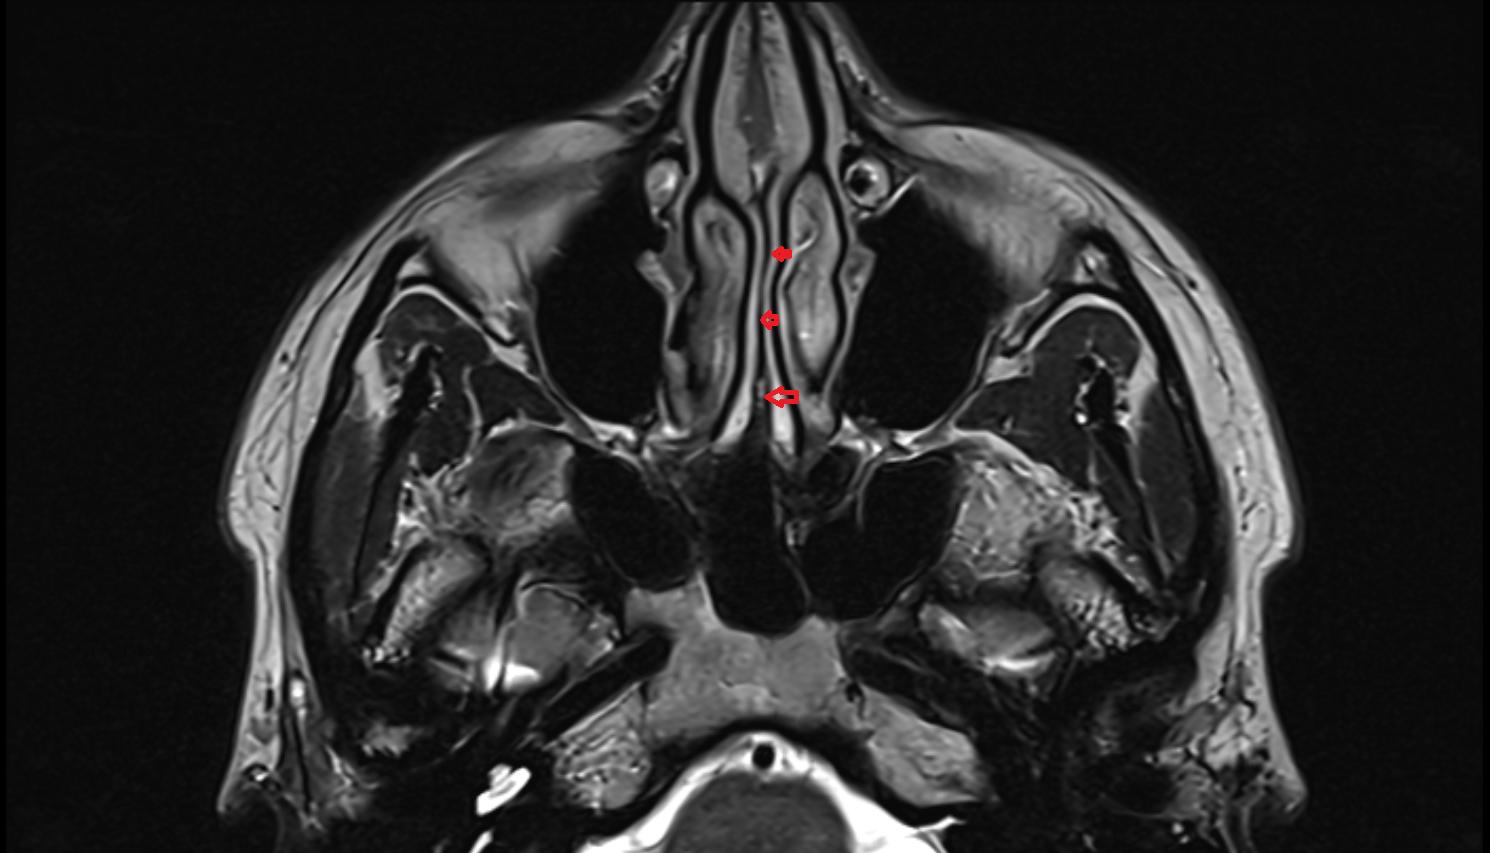

- Nasolacrimal duct (Tear duct)